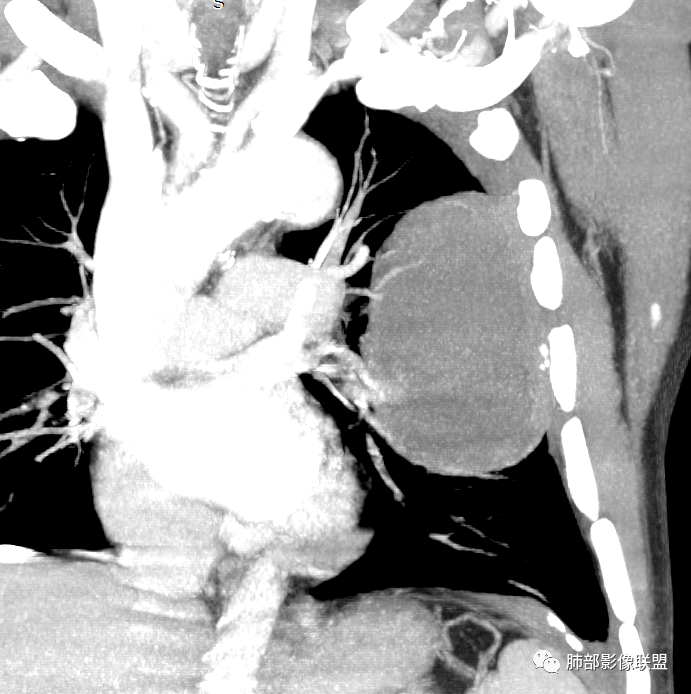

我再建一下血管。支气管进入,但是近端推移,堵塞

大肿块,边缘光滑,深分叶

近端支气管堵塞、推移为主

部分类似于脐凹征

内部支气管扩张

肺动脉推移为主,边缘部分进入

淋巴瘤符合吗?

大肿块、表面光滑但深分叶,肺门侧支气管堵塞

我一开始诊断恶性,定在淋巴瘤,还觉得信心满满

回头看,内部支气管近端其实不连续,伴随肺动脉不存在

这两点就不符合

5)肿瘤强化方式:肺部恶性肿瘤强化程度与其血供丰富程度相关,血供丰富多强化明显,反之则较差。由于PSC 周边实性部分富血供及内部黏液变性、坏死,增强后肿块多数呈轻-中度边缘环形强化或不均匀小斑片状强化。国外学者对照病理发现肿瘤细胞或胶原组织增强扫描时强化,无强化的低密度区代表了黏液样变性区和出血坏死区。